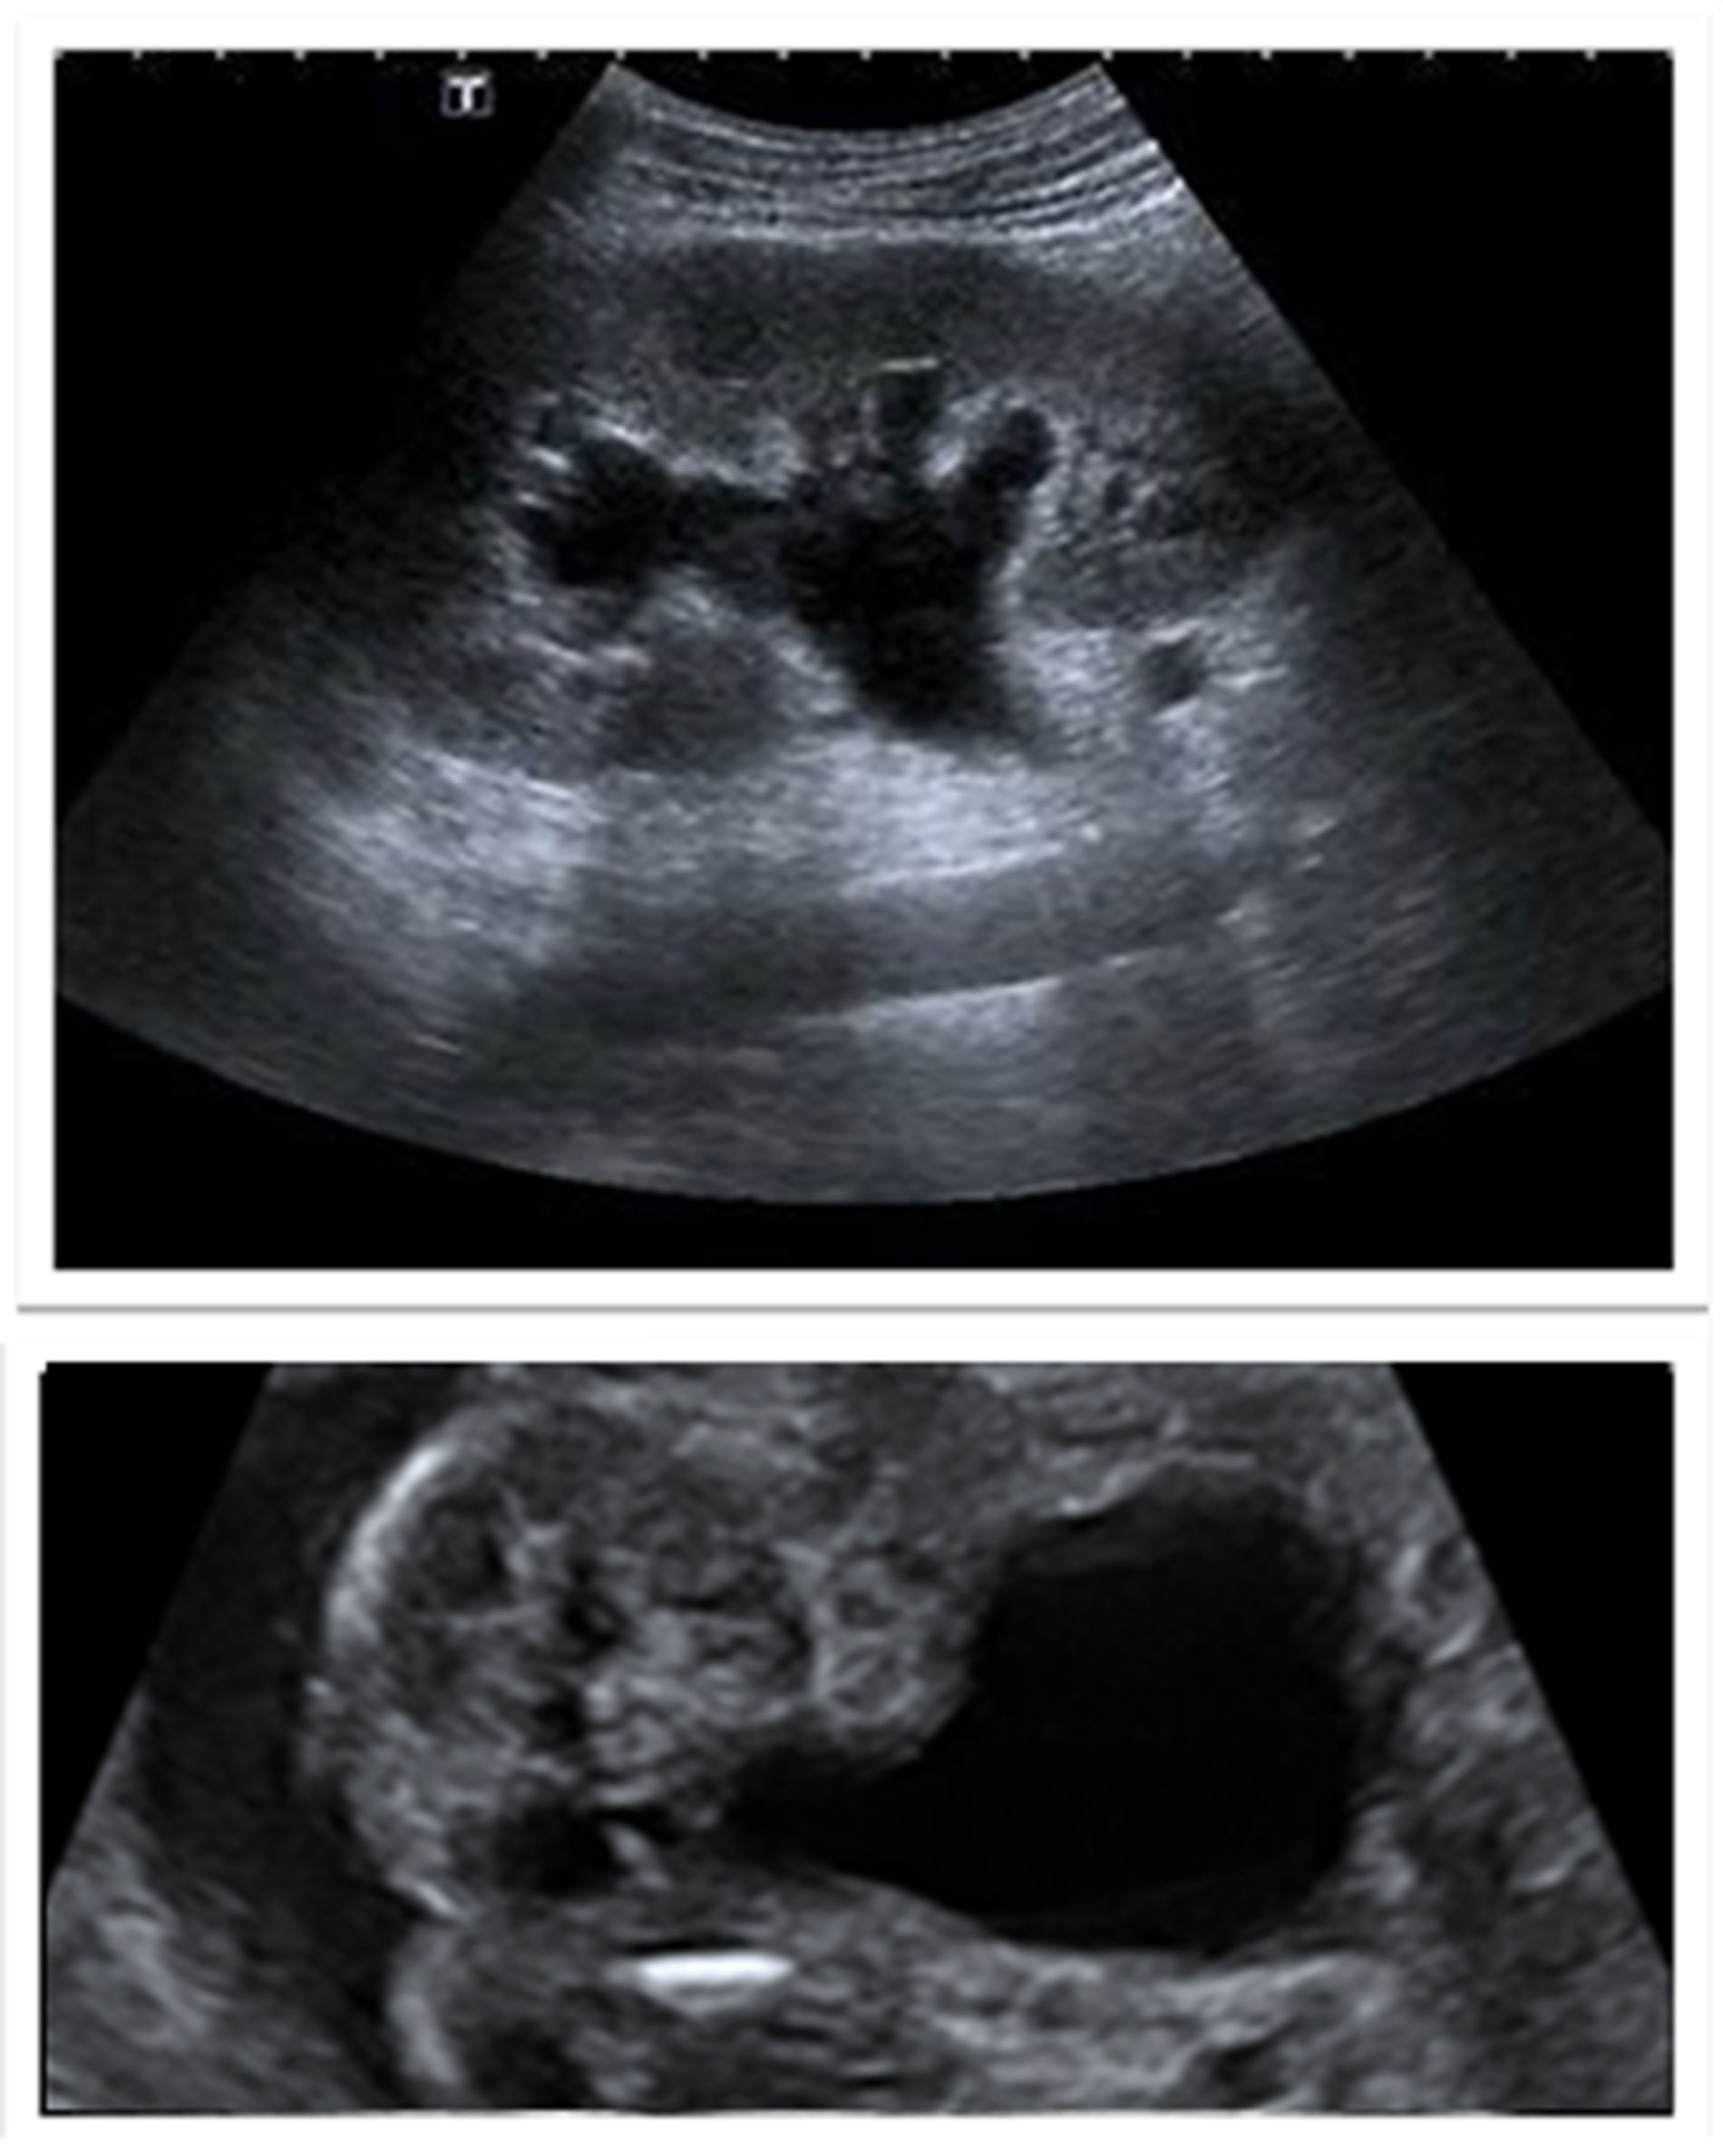

The index case is typically identified on antenatal ultrasound scan, or early postnatally. Ultrasound shows bilateral hydroureteronephrosis, distended and thick-walled bladder and dilated posterior urethra with the characteristic keyhole sign. These findings are generally confirmed by a micturating cystourethrogram (MCUG) performed after birth. Other possible signs on MCUG are bladder trabeculations, dilated posterior urethra, hypertrophied bladder neck (spinning top sign) with or without vesico-ureteric reflux (Figure 2). This index case represents the severest form of the disease, which most clinicians are familiar with. However, milder cases that present during late childhood, may not demonstrate all these cardinal signs [4].

Figure 2: Top: ultrasound scan images showing hydronephrosis, and key-hole sign.

Bottom: MCUG showing dilated posterior urethra with transition point at level of PUV, and high grade reflux.